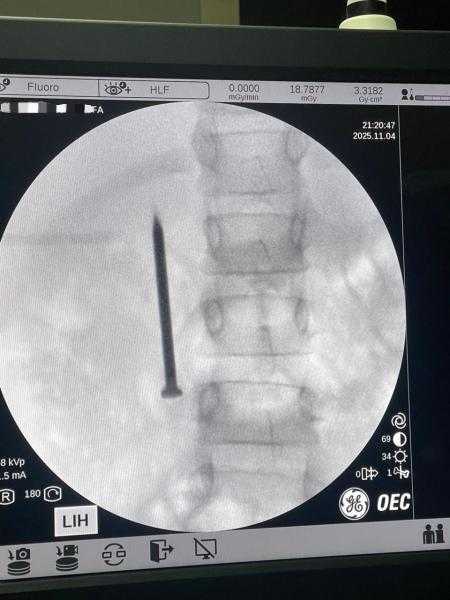

نجاح فريق طبي بمعهد الكبد القومي بجامعة المنوفية في استخراج مسمار حاد من أمعاء طفلة ٧...